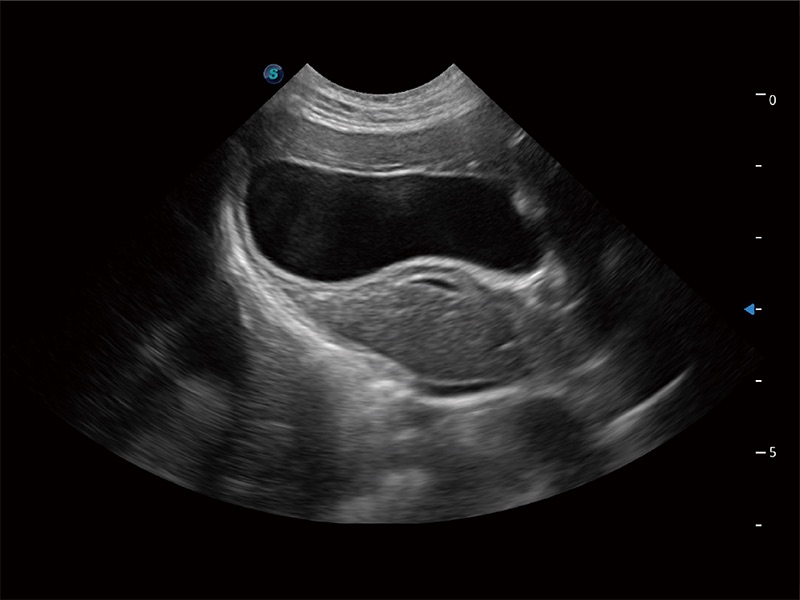

动物是人类最亲密的朋友和最值得信赖的伙伴。银河优越会也一直致力于探索动物专用的超声影像解决方案。全新推出的ProPet系列,是银河优越会在动物超声影像智能化、专业化、精准化的一次跨越式革新。动物不能用言语来表述自己的不适,通过超声影像,ProPet系列搭建了动物医生与不同物种沟通的“桥梁”,为动物医生注入了“治愈之力”。 ProPet 80 是银河优越会匠心打造的一款高端动物专用彩超,采用性能卓越的全新硬件架构,极大提升超声系统的运行效率和数据处理能力,帮助动物医生从容应对日益增多的挑战性病例和日益多样化的临床需求。

高性能和先进的临床应用工具可以为动物医生提供临床信心。ProPet 80 搭载了先进的腹部和浅表应用工具,帮助医生在日常临床实践中发挥前所未有的作用。

一键自动识别膀胱壁及自动测量膀胱容积,不受膀胱形状和大小的限制,帮助医生快速精准获得测量的数据。